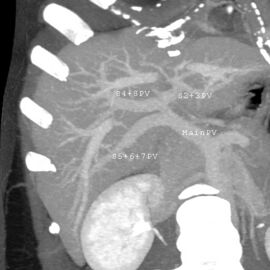

فحص بالتصوير المقطعي المحوسب يظهر فيه الكبد والوريد البابي.

With the recent advances of noninvasive imaging, living liver donors usually have to undergo imaging examinations for liver anatomy to decide if the anatomy is feasible for donation. The evaluation is usually performed by multidetector row computed tomography (MDCT) and magnetic resonance imaging (MRI). MDCT is good in vascular anatomy and volumetry. MRI is used for biliary tree anatomy. Donors with very unusual vascular anatomy, which makes them unsuitable for donation, could be screened out to avoid unnecessary operations.

MDCT image. Portal venous anatomy contraindicated for liver donation